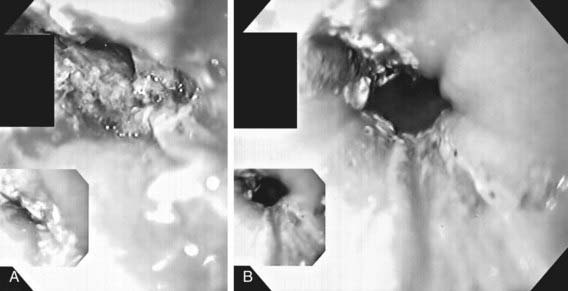

Evaluation of the child with a history of foreign body ingestion starts with plain anteroposterior (AP) radiographs of the neck, chest, and abdomen, along with lateral views of the neck and chest. The flat surface of a coin in the esophagus is seen on the AP view and the edge on the lateral view (Fig. 319-1). The reverse is true for coins lodged in the trachea; here, the edge is seen anteroposteriorly and the flat side is seen laterally. Disk batteries can look like coins (Fig. 319-2) and have a much higher risk of burns and necrosis (Fig. 319-3). Materials such as plastic, wood, glass, aluminum, and bones may be radiolucent; failure to visualize the object with plain films in a symptomatic patient warrants urgent endoscopy. Although barium contrast studies may be helpful in the occasional asymptomatic patient with negative plain films, their use is to be discouraged because of the potential of aspiration as well as making subsequent visualization and object removal more difficult.

image

Figure 319-2 Disk battery impacted in esophagus. Note the double rim.

(From Wyllie R, Hyams JS, editors: Pediatric gastrointestinal and liver disease, ed 3, Philadelphia, 2006, Saunders.)